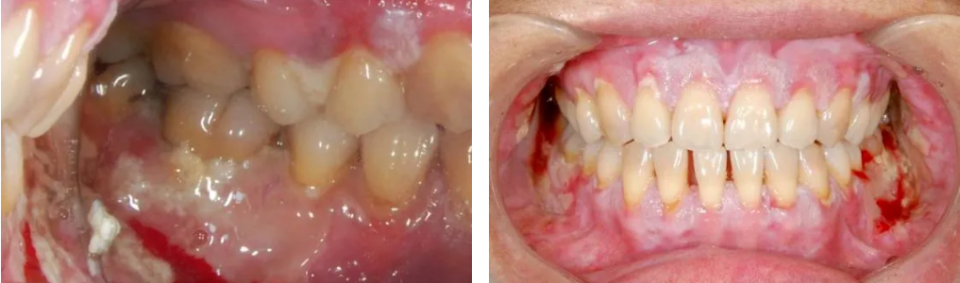

4、牙周与牙齿

口腔症状共同导致了一个恶性循环:因疼痛而畏惧清洁,因张口受限而清洁不到位,因口干而失去唾液的自洁与保护,导致牙周炎症加重和龋齿5、11。口腔健康状况的急剧恶化,反过来又加重了感染风险和全身负担。

龋齿表现(图片源自陶人川教授团队)